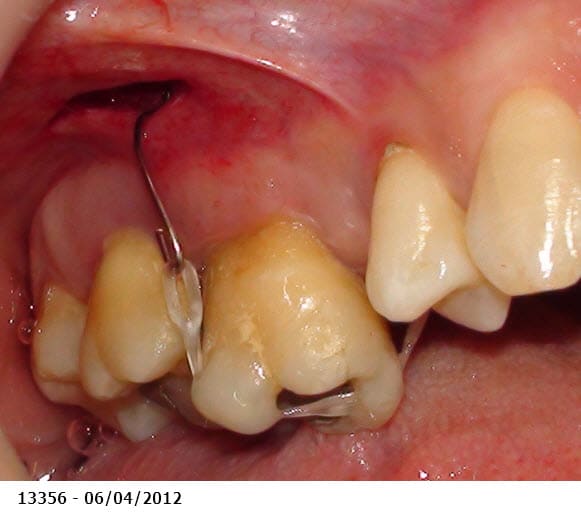

Je sèche un peu sur ce cas, auriez vous un avis SVP.

Patiente moins de 40 ans, qui a un peu laissé trainer les choses et désire s'en occuper maintenant. Elle pensait avoir droit aux complets mais je lui ai tout de suite dit "mais nooooooooon !". Possibilités financières limitées (pas d'implanto).

Les égressions dues au manque de calage postérieur sont ici extrêmes. La dévitalisation + élongation coronaire + couronnes ou bridges plus ou moins dans la courbe de Spee des molaires maxillaires, risque de me faire atteindre les furcations.

Est-ce qu'un ortho pourrait ingresser ces molaires maxillaires?

La seule solution viable est chirurgicale et implantaire car en plus les molaires sup ont déjà une grosse perte osseuse (furcation sur la 27 ? - parodontite chronique ?) donc pas de plastie osseuse possible en conservant les dents postérieures.

PS2: et devant, esthétiquement, c'est comment ?

les papilles n'ont pas l'air au mieux de leur forme